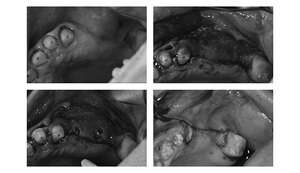

【担当医師所見】

治療前、左上大臼歯部は咬合面(咬む面)も無くカリエス(虫歯)も大きいものでした。

治療後、理想的な位置にインプラントが埋入され正しく咬むことができるようになりました。